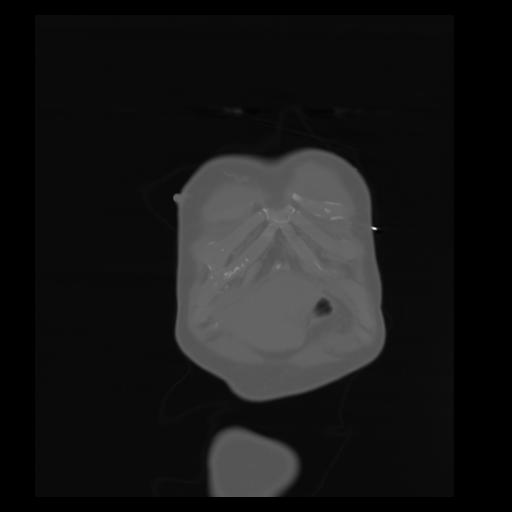

29 CUERPO,CE,Coronal,3.000,CUERPO,Coronal,